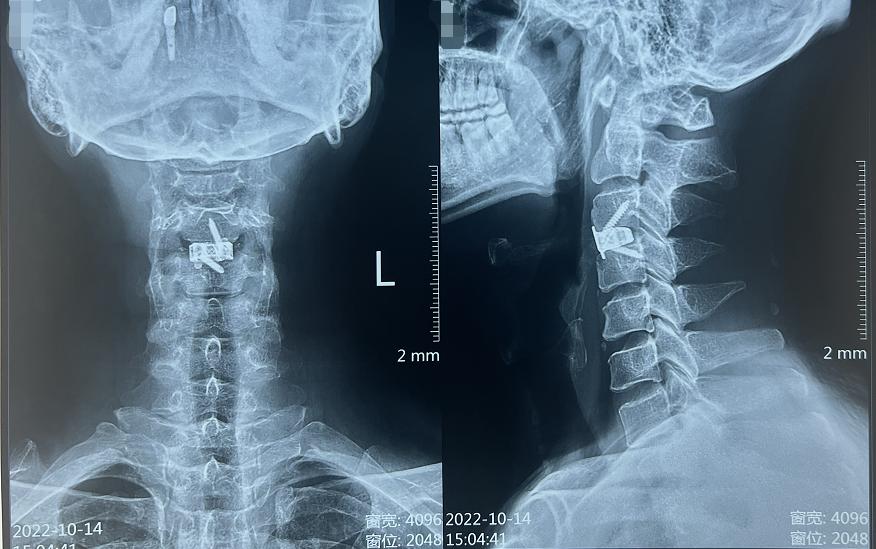

那到底是什么问题导致刘先生出现这些严重症状呢?经过核磁共振等影像学检查后,我们发现刘先生的颈3/4椎间盘出现了突出,并且已经严重压迫到脊髓,建议他尽快考虑手术减压。

针对于刘先生的这些顾虑,再紧密结合他具体的病情,最终我们为他制定了单节段的颈椎前路间盘切除减压融合术,并决定进行Langer's lines横切口,做一个美容缝合。这种手术在显微镜下进行,从颈椎前方入路利用自然解剖间隙达到突出椎间盘的节段,进行脊髓减压操作,安全有效。术中对患者的脊髓、神经、肌肉、血管等创伤很小,术后患者恢复快、住院时间段。

我们为刘先生尽快安排了手术。因为他是颈3/4的椎间盘突出,节段较高,进行高位颈椎横切口,还是稍费了些功夫,但是好处是手术微创,术后切口美观。术中给受压脊髓进行了精准、彻底地减压后,成功地进行了固定融合,将3D打印融合器与终板完美贴合,手术圆满完成。